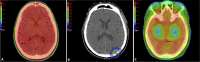

Brain metastases are the most common intracranial neoplasm and are seen in upwards of 10-30% of patients with cancer. For decades, whole brain radiation therapy (WBRT) was the mainstay of treatment in these patients. While WBRT is associated with excellent rates of intracranial tumor control, studies have demonstrated a lack of survival benefit, and WBRT is associated with higher rates of cognitive deterioration and detrimental effects on quality of life. In recent years, strategies to mitigate this risk, such as the incorporation of memantine and hippocampal avoidance have been employed with improved results. Furthermore, stereotactic radiosurgery (SRS) has emerged as an appealing treatment option over the last decade in the management of brain metastases and is associated with superior cognitive preservation and quality of life when compared to WBRT. This review article evaluates the pathogenesis and impact of cranial irradiation on cognition in patients with brain metastases, as well as current and future risk mitigation techniques.